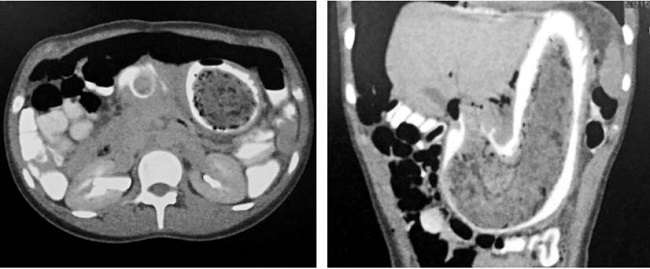

Se realiza una tomografía axial computarizada (TAC) de abdomen, con doble contraste, que muestra la cámara gástrica distendida y ocupada por una lesión de densidades variables, las cuales dan paso parcial al medio de contraste. Luego de valorar los hallazgos radiográficos, se decide efectuar una esofagogastroduodensocopia, en la cual se evidencia la presencia de un conglomerado compacto, compuesto por un cuerpo extraño (bezoar), que ejerce un efecto obstructivo a nivel distal y que se expande desde el cardias hasta más allá de la cuarta porción duodenal (Figura 1).

Así, el diagnóstico endoscópico permite el hallazgo de un cuerpo extraño intragástrico de tipo bezoar que, al ocupar la cámara gástrica y el duodeno en su totalidad, configura un síndrome de Rapunzel (Figura 2).

Asimismo, dentro de los estudios diagnósticos que pueden realizarse se hallan la TAC con contraste y la esofagogastroduodenoscopia. Para el caso del síndrome de Rapunzel, en la TAC suele observarse una lesión bien circunscrita a nivel gástrico, compuesta de espirales concéntricas de diferentes densidades y burbujas de aire enredadas dentro de ellas. El contraste oral llena los intersticios más periféricos de la lesión, lo que produce una banda delgada de contraste que la circunscribe 11.